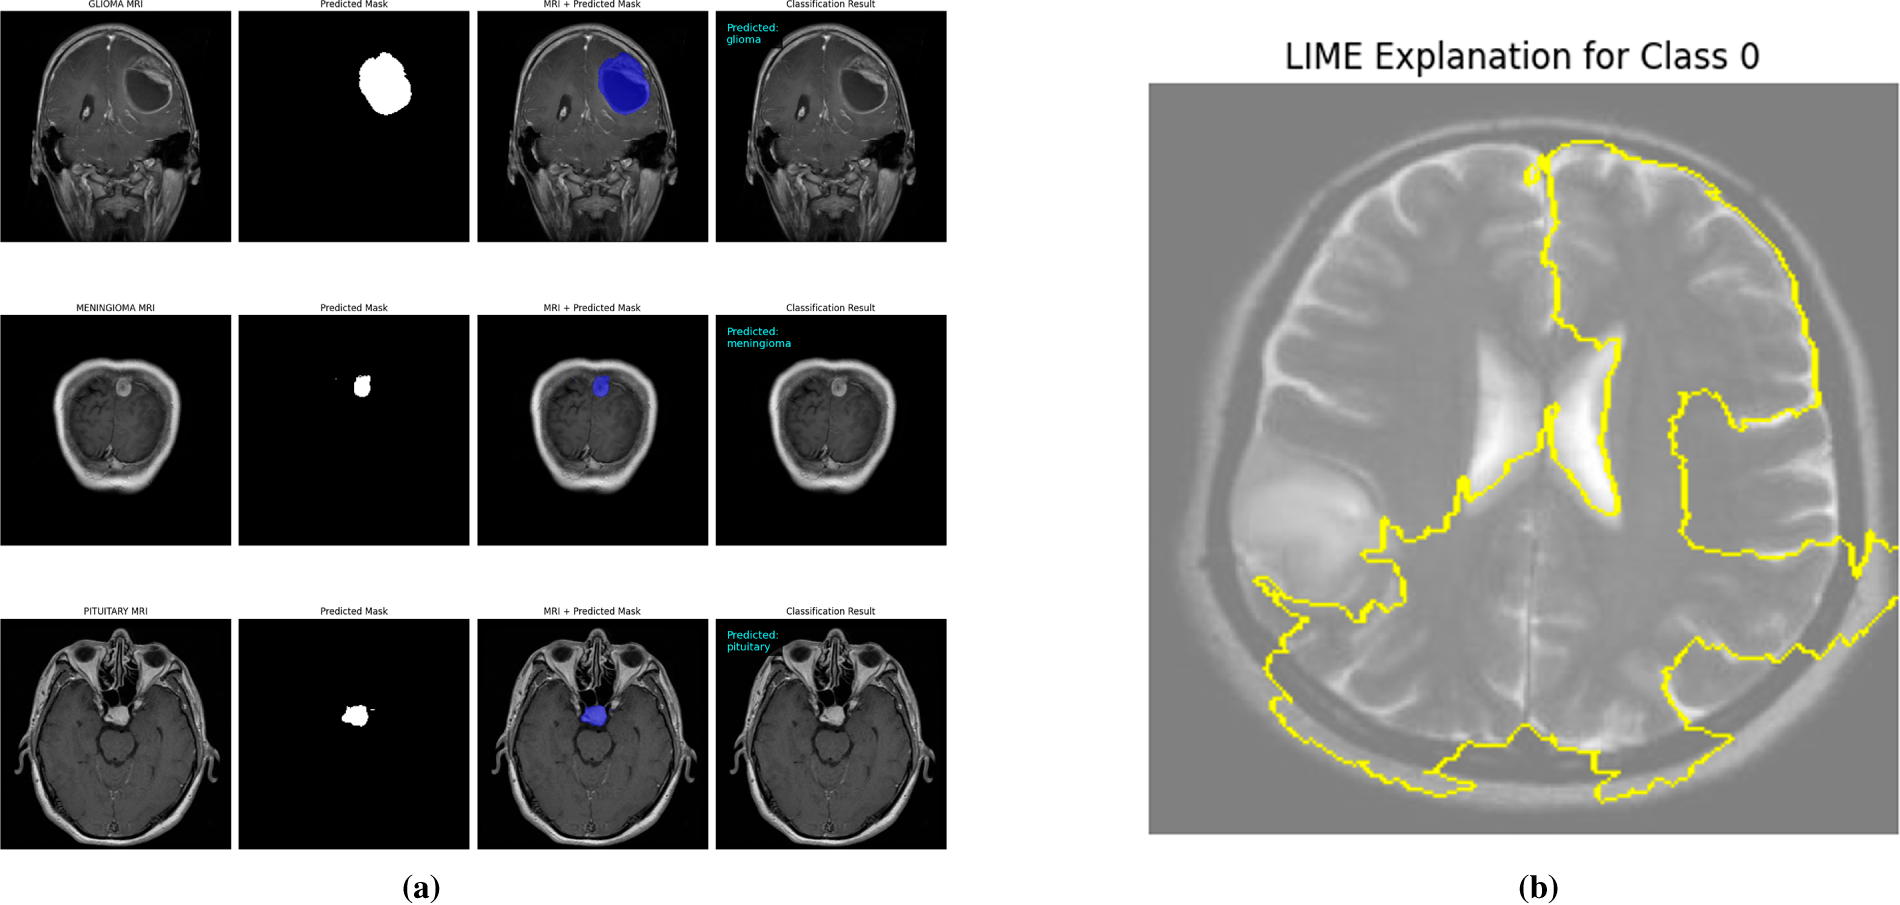

The interpretability of the student model was analyzed using Grad-CAM and LIME visualizations, complemented by faithfulness scores (Insertion and Deletion metrics) computed over 10 representative images per class. These analyses were conducted after achieving state-of-the-art accuracy, thereby confirming that high predictive performance aligns with stable interpretability. The confidence scores of the sampled images remained consistently high (average 0.99), indicating strong predictive certainty of the model. Grad-CAM visualizations (Fig. 9) clearly highlight the spatial regions with the greatest impact on predictions across all four classes, including normal, glioma, pituitary, and meningioma, accurately localizing tumor regions and supporting the model’s structural focus. LIME results (Fig. 10b) further delineate superpixels contributing to model decisions, while class-specific masks (Fig. 10a) were generated solely for visualization in the faithfulness evaluation, not for training purposes.

Figure 10: Visual explanations for student models after knowledge distillation. (a) Class-specific masks highlighting regions of interest for the MobileNetV2 student, illustrating model attention for each tumor type. (b) LIME-based explanations showing the predictive regions for the EfficientNet-L0 student, providing interpretable insights into model decisions.

Table 7 presents the Insertion and Deletion scores for both Grad-CAM and LIME. Notably, the normal class shows a low deletion score of 0.09 for Grad-CAM because removing non-informative regions in a normal brain has minimal effect on prediction, reflecting the absence of critical features to disrupt the model’s confident classification. Across all classes, the average insertion and deletion scores confirm that the highlighted regions consistently correspond to the model’s confident predictions (Insertion: 0.69 Grad-CAM, 0.73 LIME; Deletion: 0.45 Grad-CAM, 0.59 LIME).

In summary, combining Grad-CAM, LIME, and mask-based faithfulness metrics provides a comprehensive interpretability framework, ensuring transparency, high diagnostic accuracy, and confidence in both teacher and student models for neurodiagnostic applications.